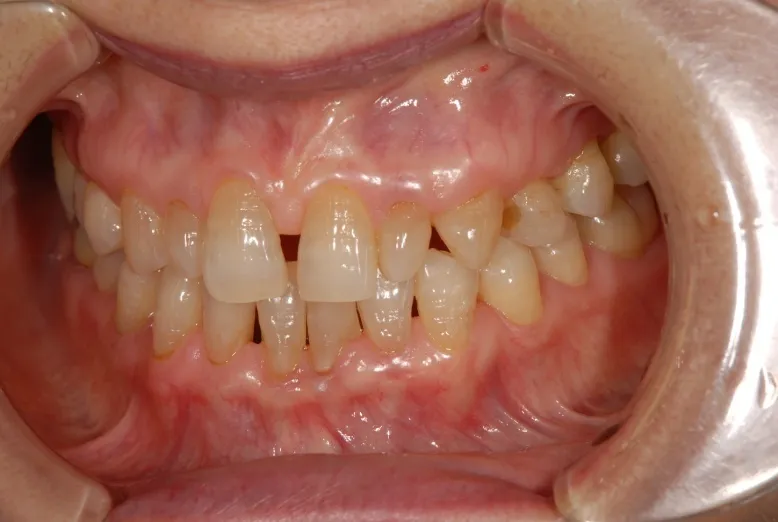

こんなふうになれば良いな・・・

治療後

治療その後

術後4ヶ月

予定合成写真